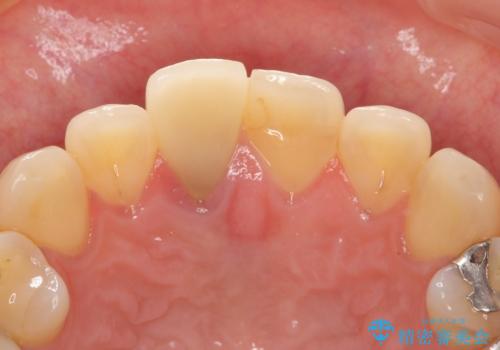

患者様の天然歯はグラデーションがあり切縁(歯冠の先端)はやや透けていて透明感があるのに対し、前歯(右上1)の差し歯はやや黄色く不透明で単調な色味でした。

患者様のご希望により、右上1はジルコニアクラウン(スペシャル)、右上5はジルコニアクラウン(スタンダード)へやりかえることにしました。

再根管治療に関しては、患者様がご希望されず症状もないため行っておりません。

ご予算の都合とご希望により、右上5の土台はやりかえずに元の土台のまま治療を進めました。

前歯のクラウンは一度修正し、患者様の理想とする色味や形態を追求しました。

右上1:ジルコニアクラウン スペシャル

右上5:ジルコニアクラウン スタンダード